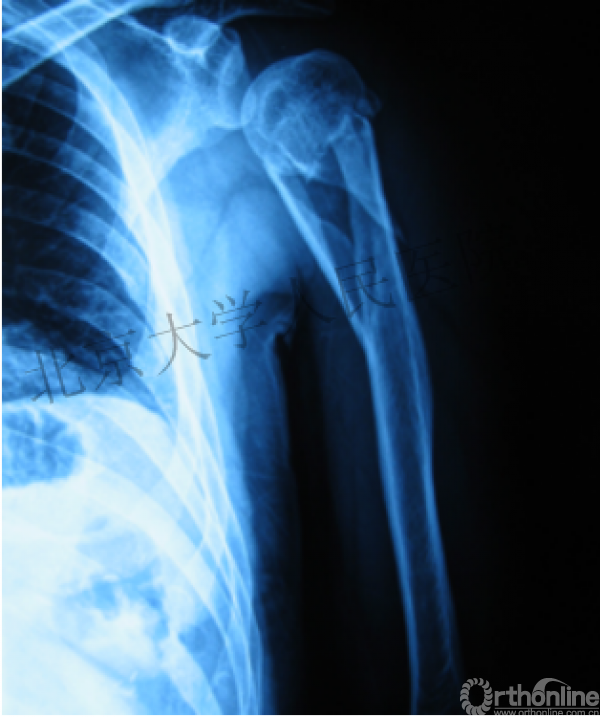

内侧皮质粉碎,低位外科颈骨折,肱骨头-干角维持困难。

术后复位丢失,肱骨头内翻畸形。

能否该偏心固定(钢板)为髓内固定,增加力臂?

早知今日,何必当初?

此时对比髓内钉是不是有很大优势?